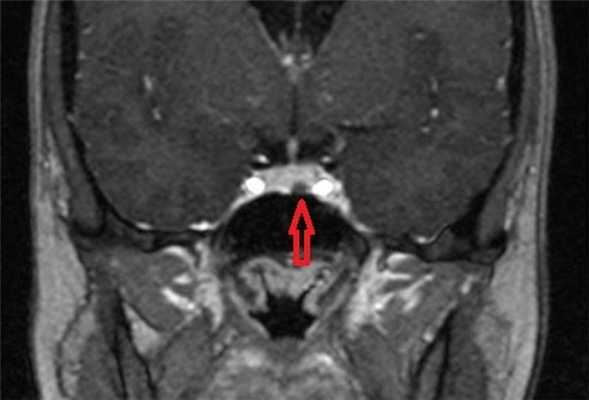

МРТ гипофиза с контрастом. После введения контрастного вещества в гипофизе происходит его накопления и он выглядит светлым. Только участок опухоли не накапливает контрастное вещество и выглятит темным (стрелка).